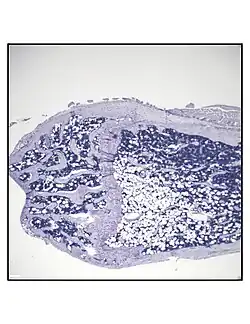

Bone marrow adipocytes are derived from mesenchymal stem cell (MSC) differentiation.

In order to understand the physiology of BMAT, various analytic methods have been applied. BMAds are difficult to isolate and quantify because they are interspersed with bony and hematopoietic elements. Until recently, qualitative measurements of BMAT have relied on bone histology,[51][52] which is subject to site selection bias and cannot adequately quantify the volume of fat in the marrow. Nevertheless, histological techniques and fixation make possible visualization of BMAT, quantification of BMAd size, and BMAT's association with the surrounding endosteum, milieu of cells, and secreted factors.[53][54][55]